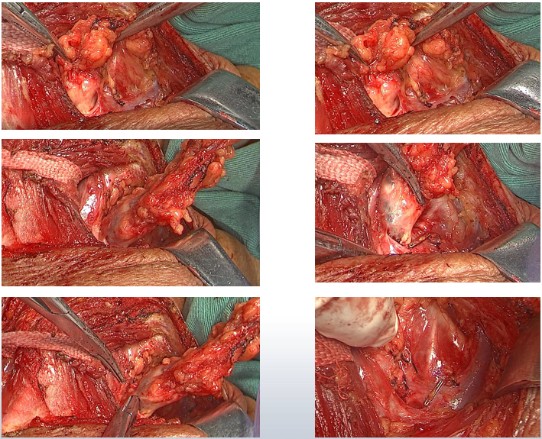

入院后,评估患者为局部晚期,潜在可手术,通过沟通,患者综合考虑后决定参与科里临床试验,使用信迪利单抗联合化疗进行治疗。2019年6月13—7月26日,行白蛋白结合型紫杉醇(200mg,d1、d8,q3w)+卡铂(0.4g,d1)+信迪利单抗 (200mg,d1,q3w)方案治疗2周期。1周期治疗后,患者吞咽困难较前改善,考虑临床部分缓解(PR)。继续行1周期治疗后,复查CT疗效评价为PR。如图。

考虑到新辅助治疗有效,在进行术前评估后,于2019年08月20日行胸腹腔镜联合食管癌切除+胃代食管左颈吻合+颈胸腹三野淋巴结清扫+空肠造瘘术+右上肺楔形切除术。如图。

术后病理结果:(食管)原瘤床经全部取材镜下见小灶鳞状上皮呈高级别上皮内瘤变,间质纤维组织增生伴慢性细胞浸润。病理结果显示到达MPR, “食管切端”胃切端未见肿瘤。各组淋巴结未见转移癌(注:左锁骨上淋巴结病理转阴)。(右上肺结节)镜下见坏死结节。

结果显示,术前新辅助治疗取得很好的疗效,影像学检查提示病灶明显缩小,评价PR。术后病理提示肿瘤退缩明显,对治疗反应良好。